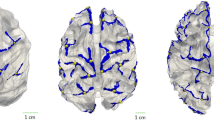

The variability in cortical morphology across subjects makes it difficult to develop a general atlas of cortical sulci. In this paper, we present a data-driven technique for automatically learning cortical folding patterns from MR brain images. A local image feature-based model is learned using machine learning techniques, to describe brain images as a collection of independent, co-occurring, distinct, localized image features which may not be present in all subjects. The choice of feature type (SIFT, KLT, Harris-affine) is explored with regards to identifying cortical folding patterns while also uncovering their group-related variability across subjects. The model is built on lateral volume renderings from the ICBM dataset, and applied to hemisphere classification in order to identify patterns of lateralization based on each feature type.